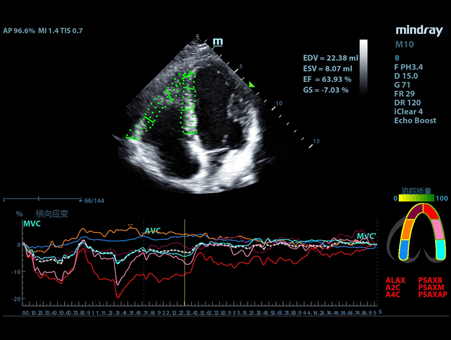

MindrayŌĆśs critical Ultrasound solutions drive improvements in care quality. Integrating advanced hemodynamic Ultrasound features, we can guarantee the highest standard of clinical care. The unique interoperability of Ultrasound and Vital sign data, we can provide comprehensive patient status data, to help inform clinical decisions, enhance clinical efficiency and, ultimately, improve patient outcomes.